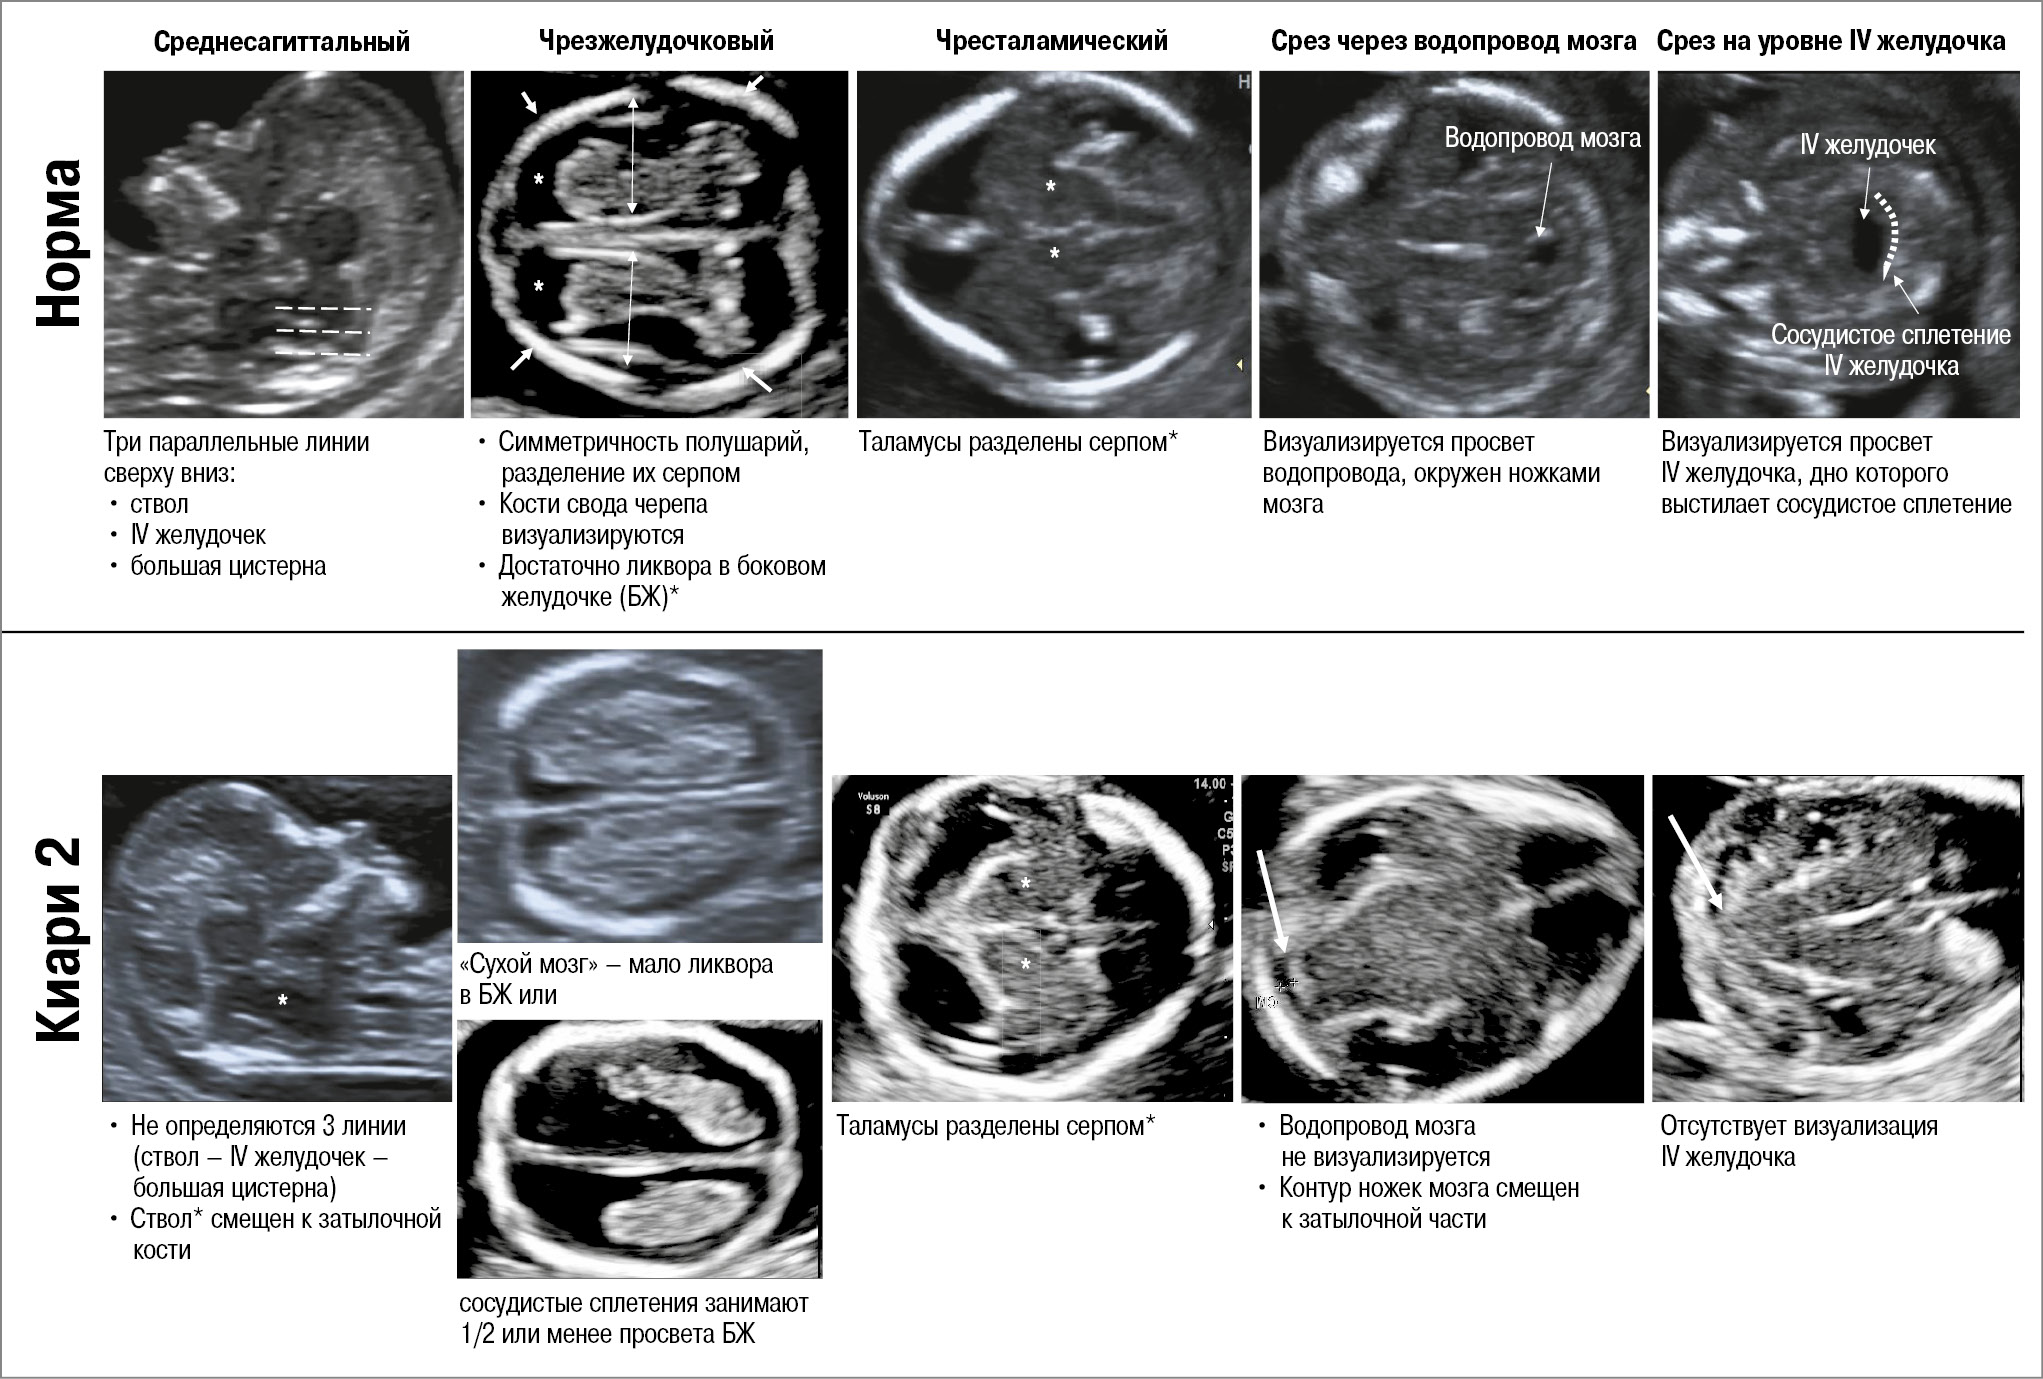

Методики ультразвуковой оценки структур ЦНС в I триместре беременности. Мозговые структуры плода в I триместре беременности оцениваются в трех плоскостях: аксиальной, сагиттальной и коронарной. В средне-сагиттальной плоскости пропорциональное соотношение структур: ствол – IV желудочек – большая цистерна, а именно визуализация их в виде трех параллельных линий, рассматривается как норма (рис. 2). В аксиальной плоскости оцениваются следующие эхографические срезы ГМ: чрезжелудочковый, чресталамический, срез через водопровод мозга и срез через IV желудочек. Факт смещения заднего края сильвиева водопровода к контуру затылочной кости и отсутствие визуализации IV желудочка в аксиальном срезе, а также уменьшение расстояния между задним контуром ствола и затылочной костью в сагиттальном срезе являются маркерами открытого спинального дизрафизма, что требует прицельного изучения позвоночника.

Рис. 2. Ультразвуковые признаки открытой spina bifida в I триместре беременности (11–14 нед). Оценка ГМ.